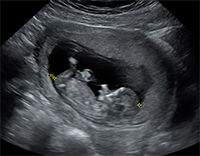

Omphalocele (pronounced OHM-fal-o-seal) is a birth defect that affects the abdominal wall. When the abdominal wall doesn’t form correctly, the bowel and other abdominal organs can be partially within the umbilical cord and covered by a thin membrane.

In a normally developing fetus, as the bowel grows, it will move into the umbilical cord until about 10 weeks, and return to the abdomen by 11 weeks. If the bowel does not move back into the abdomen and stays within the umbilical cord, an omphalocele occurs.

How is Omphalocele Monitored During Pregnancy?

Our team will follow your pregnancy closely with ultrasounds and fetal monitoring (non-stress testing) to assess your babies well-being and plan for delivery.

Over the past five years, UR Medicine's Maternal-Fetal Medicine has cared for and evaluated more than 50 fetuses with omphalocele diagnosed in utero. Our OB/GYN ultrasound unit is certified by the American Institute of Ultrasound in Medicine to perform Level II ultrasounds, a more in-depth evaluation.

Our experienced Registered Diagnostic Medical Sonographers and state-of-the-art equipment including 3D/4D capabilities help diagnose omphalocele effectively.